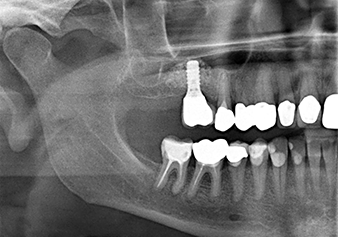

A 49-year-old female patient, a non-smoker and with nothing remarkable in her general medical history, was referred to our oral surgery practice for surgical extraction of tooth 16 and subsequent implantation. After the extraction, the patient experienced mild sinusitis trouble with the resultthat we initially waited six months before carrying out the measure. The residual bone height at the planned implant position measured 3-4 mm (Fig. 1 and 2).

Fig.2: The DVT shows adequate dimensions in each of the axial (left), lateral (top) and transverse views (right). The maxillary sinus membrane is still slightly thickened.